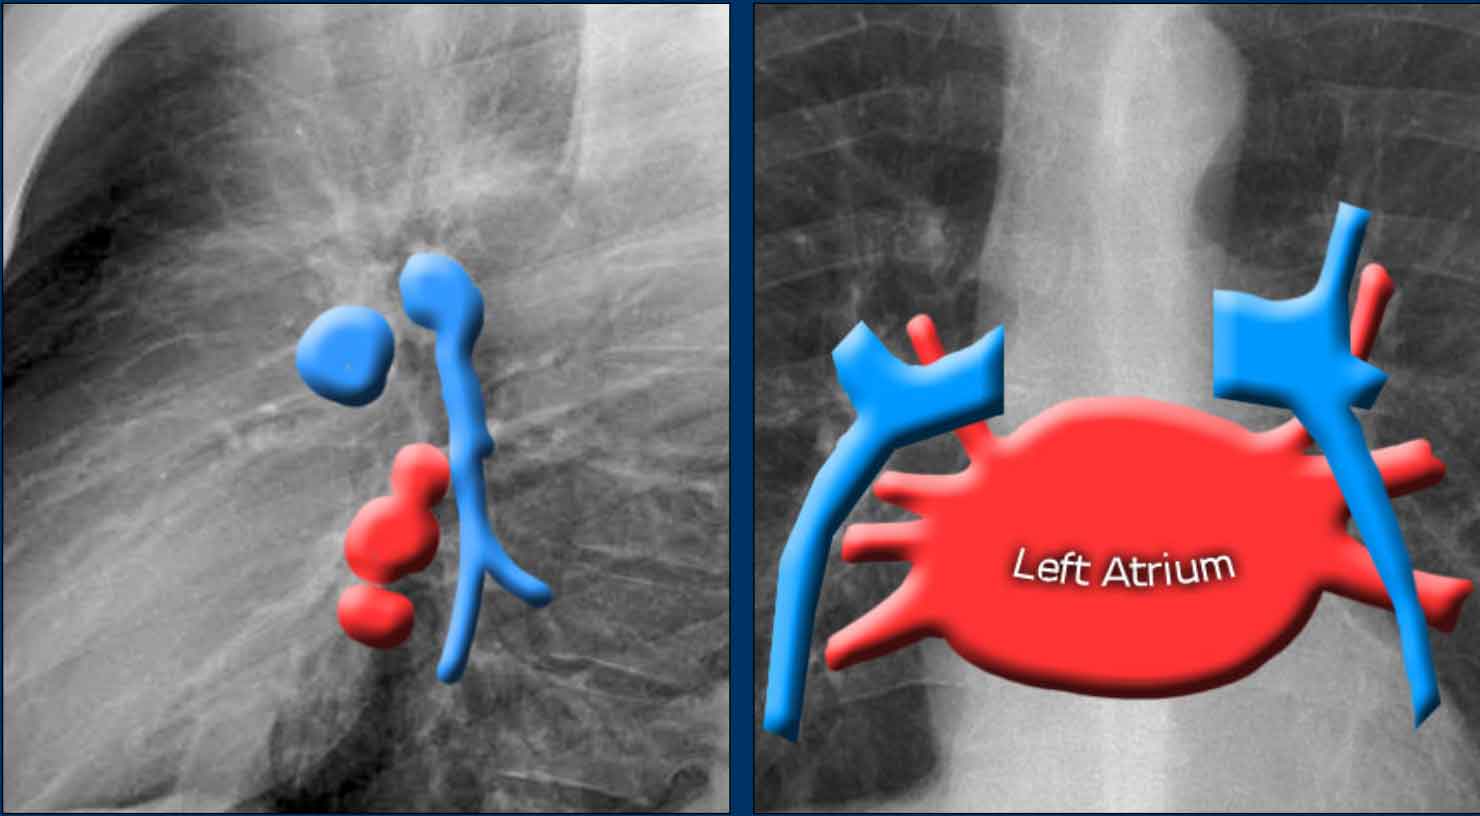

Left Atrium (LA)

It is the most posterior cardiac chamber and it receives oxygenated blood from the pulmonary veins, which enter the left atrium almost horizontally. The left atrial appendage is occasionally visible as a small outpouching just below the pulmonary trunk (best seen on lateral view).

Radiographic signs of left atrial enlargement:

• PA view: Bulging of the upper right heart border and widening of the carinal angle due to splaying of the main bronchi.

• Lateral view: Bulging of the posterior-superior cardiac contour.

An important anatomical consideration is that the left hilum is normally situated higher than the right.

This relationship arises from the course of the pulmonary arteries: the left pulmonary artery arches over the left main bronchus, while the right pulmonary artery courses anterior to the right main bronchus, which is typically positioned lower than its left counterpart.

In a minority of cases, the hila may be at the same level, but the right hilum should never be higher than the left.

In this illustration, lower lobe pulmonary arteries are colored blue to indicate deoxygenated blood.

These arteries have a more vertical orientation compared to the pulmonary veins, which run more horizontally toward the left atrium, located inferior to the level of the main pulmonary arteries.

On lateral chest radiographs, both pulmonary arteries and veins are identifiable and should not be misinterpreted as lymphadenopathy. Occasionally, pulmonary veins may appear prominent.

The left main pulmonary artery passes superior to the left main bronchus and lies higher than the right pulmonary artery, which courses anterior to the right main bronchus.